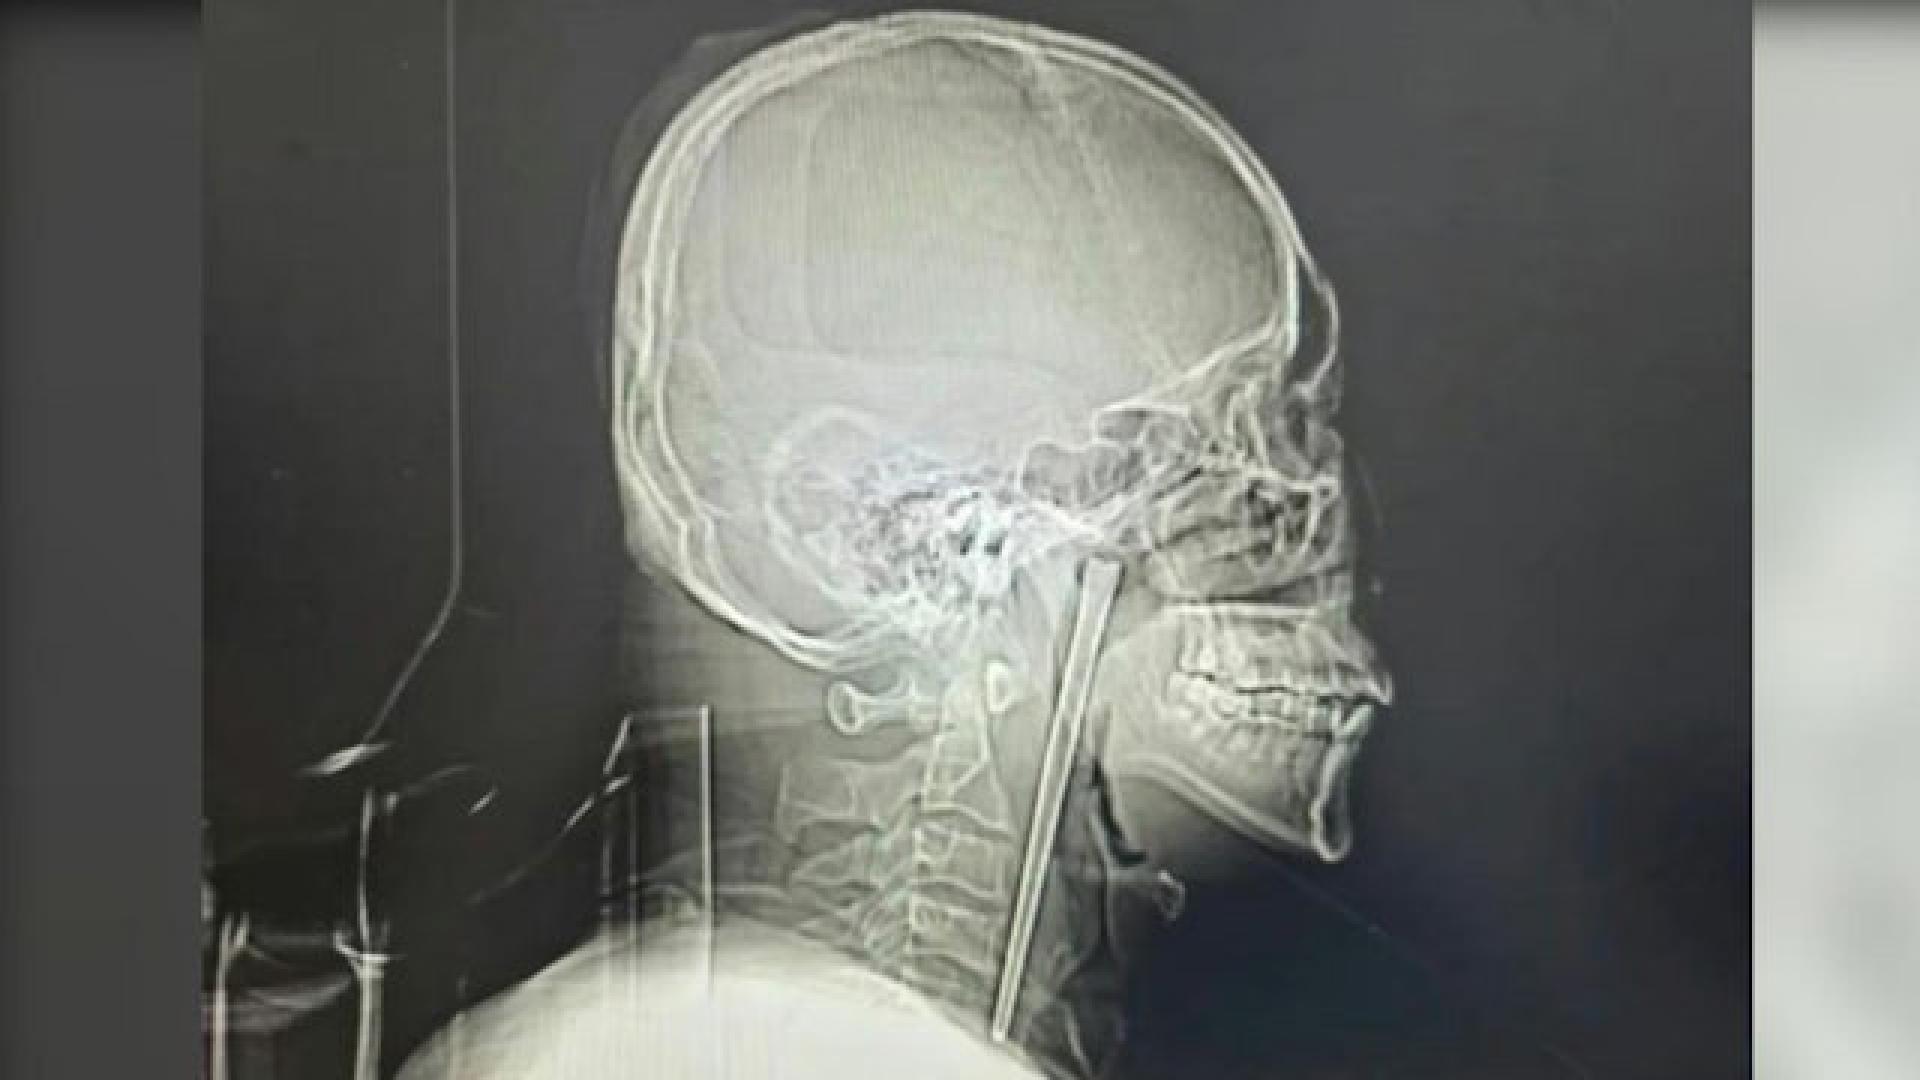

男子咽喉部竟插著一根长达12厘米的金属筷子,且已在体内留存长达8年之久。

辽宁大连一名46岁男子近日因喉咙持续不适就医,竟意外揭开一段长达8年的“体内藏筷”惊魂记。该男子在大连理工大学附属中心医院检查下,赫然发现咽喉部竟插著一根长达12厘米的金属筷子,且已在体内留存长达8年之久,离奇经历引发热议。

直到近期,该男子的咽喉疼痛感变得剧烈且难以忍受,甚至影响进食与呼吸,才前往当地医院求诊。医生透过影像检查发现,这根长达12厘米的金属异物已嵌入软颚后侧,外露约3厘米。所幸,周遭的咽喉黏膜未有明显破损、出血及发炎化脓情况,声带活动正常,喉腔结构也未受压迫移位。